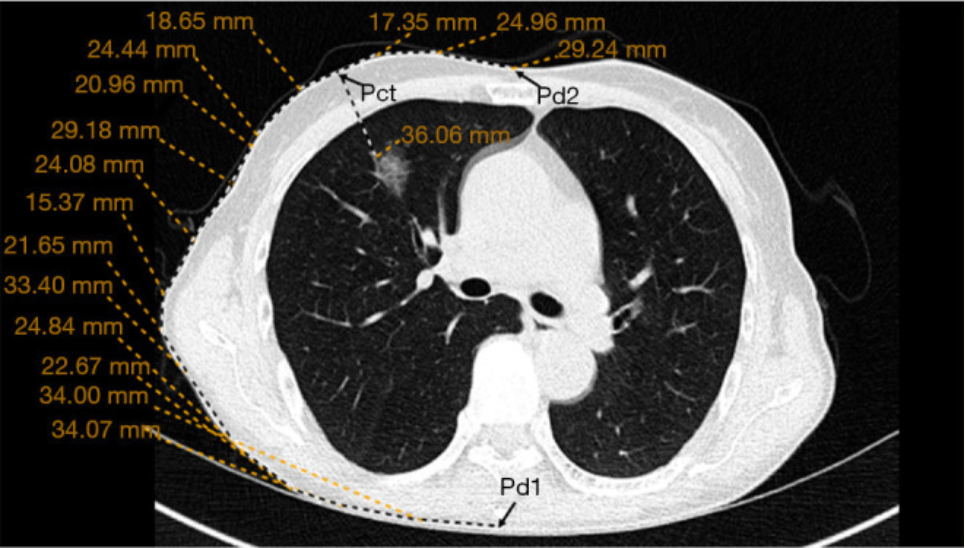

Fig. 1CT slice images and extracted bronchial structures in the inflated/deflated states.

(a) Intensity shift and topological changes inside the thoracic cavity, and

(b) the paired bronchial labels extracted using the same CT values. (Arrows indicate estimated corresponding points).